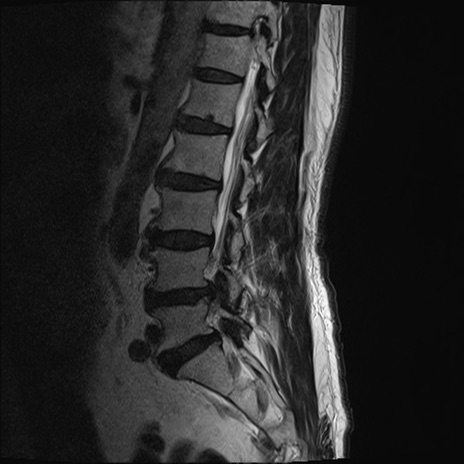

【整形】TIPS症例2 腰椎MRI T2WI(矢状断像)

【症例】70歳代男性

【主訴】左下肢痛

【現病歴】2週間前くらいから腰痛、左下肢痛あり。左臀部から大腿、下腿外側のしびれが常時ある。歩行とともに同部位の痛みあり。

【身体所見】Lasegue70-/60+、Bragard-/±、PTR ±/±、ATR -/-、IP 5/5、TA 5/4、TS 5/5、EHL 右第1足趾なし/3、FHL 5/5、hypersthesia(-)、足背動脈触知良好

異常所見と診断は?